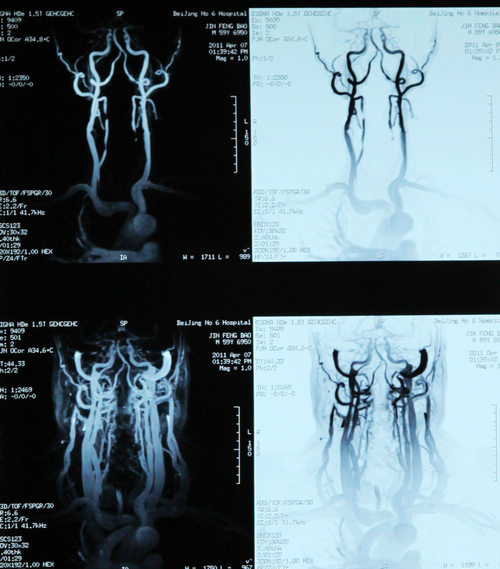

双侧颈动脉狭窄,反复头晕2年

患者金某某,男,58岁,主因反复头晕2年,加重伴左侧肢体麻木1年入院。患者2年前无明显诱因突然出现头晕,伴左侧肢体力弱,无明显头痛、恶心。呕吐,无视物旋转、耳鸣、听力下降、黑曚、晕厥、肢体抽搐,于当地医院行头颅CT检查示双侧多发腔隙性脑梗塞。给予改善脑循环、降压等药物治疗(具体不详)后症状好转。1年前无诱因再发头晕不适,伴左侧肢体麻木,偶有黑曚出现,无肢体力弱、耳鸣、视物旋转。于当地医院保守治疗后好转。住院期间行造影提示左侧颈内动脉狭窄。为进一步治疗入住北京市第六医院。

双侧颈内动脉狭窄

患者为高龄男性,“反复头晕2年,加重伴左侧肢体麻木1年”,有高血压、糖尿病、高脂血症,双侧颈内动脉狭窄,属脑卒中高发人群,实施CEA手术可有效预防卒中发作。2011年4月12日,协作组张勤奕教授及安贞医院欧阳川教授顺利为其实施了左侧颈动脉内膜剥脱术。